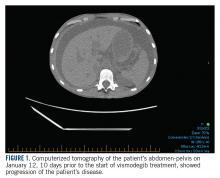

In January 2018, 2 days after receiving her first dose of nivolumab, the patient required admission for worsening abdominal pain secondary to progression of her disease ( FIGURE 1 ). She was found to have acute kidney injury on top of chronic kidney disease due to hydronephrosis requiring a left-sided double J stent. She also had transaminitis resulting from a common bile duct stricture treated with a biliary stent and worsening ascites requiring regular paracentesis. This was all in the context of new or growing metastatic implants.

At this time, the result of the FoundationOne genomic testing revealed PTCH1 loss of exons 1-24 and CDKN2A/B loss. Mutation of tumor suppressor gene PTCH1 leads to Hedgehog pathway activation and therefore the patient was started on vismodegib on January 22, 2018. She was discharged from the hospital in stable condition a day later, on January 23.